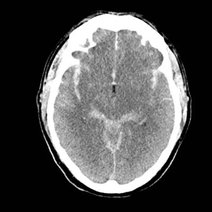

脑动脉瘤是颅内动脉血管的异常瘤状突起。脑动脉瘤不破裂,一般病人没有明显症状,如果破裂出血,常表现为蛛网膜下腔出血,病人可以出现剧烈的头痛,恶心呕吐,甚至出现...11216人收听

- 数字减影血管造影技术,颅内动脉瘤介入治疗,湘雅护理学院,颅内动脉瘤,颅内动脉瘤系指脑动脉壁的异常膨出部分,是引起自发性蛛网膜下腔出血的最常见原因。病因-尚不甚清楚,但以先天性动脉瘤占大部分。任何年龄可

- 动瘤DavidSLiebeskind1引1.1景动瘤是有破倾向的管结构的病理性局灶性扩张。些管异常常根据假定的病因分类。囊状、浆果状或先天性动瘤占全动瘤的90

- 脑动脉瘤相关知识脑动脉瘤简单说就是脑动脉血管壁上膨出的血管泡,血管泡在血液不间断的冲击下,就象吹气球一样,球吹得越大,血管壁就变得越薄,血管也就越容易破裂。一般认为